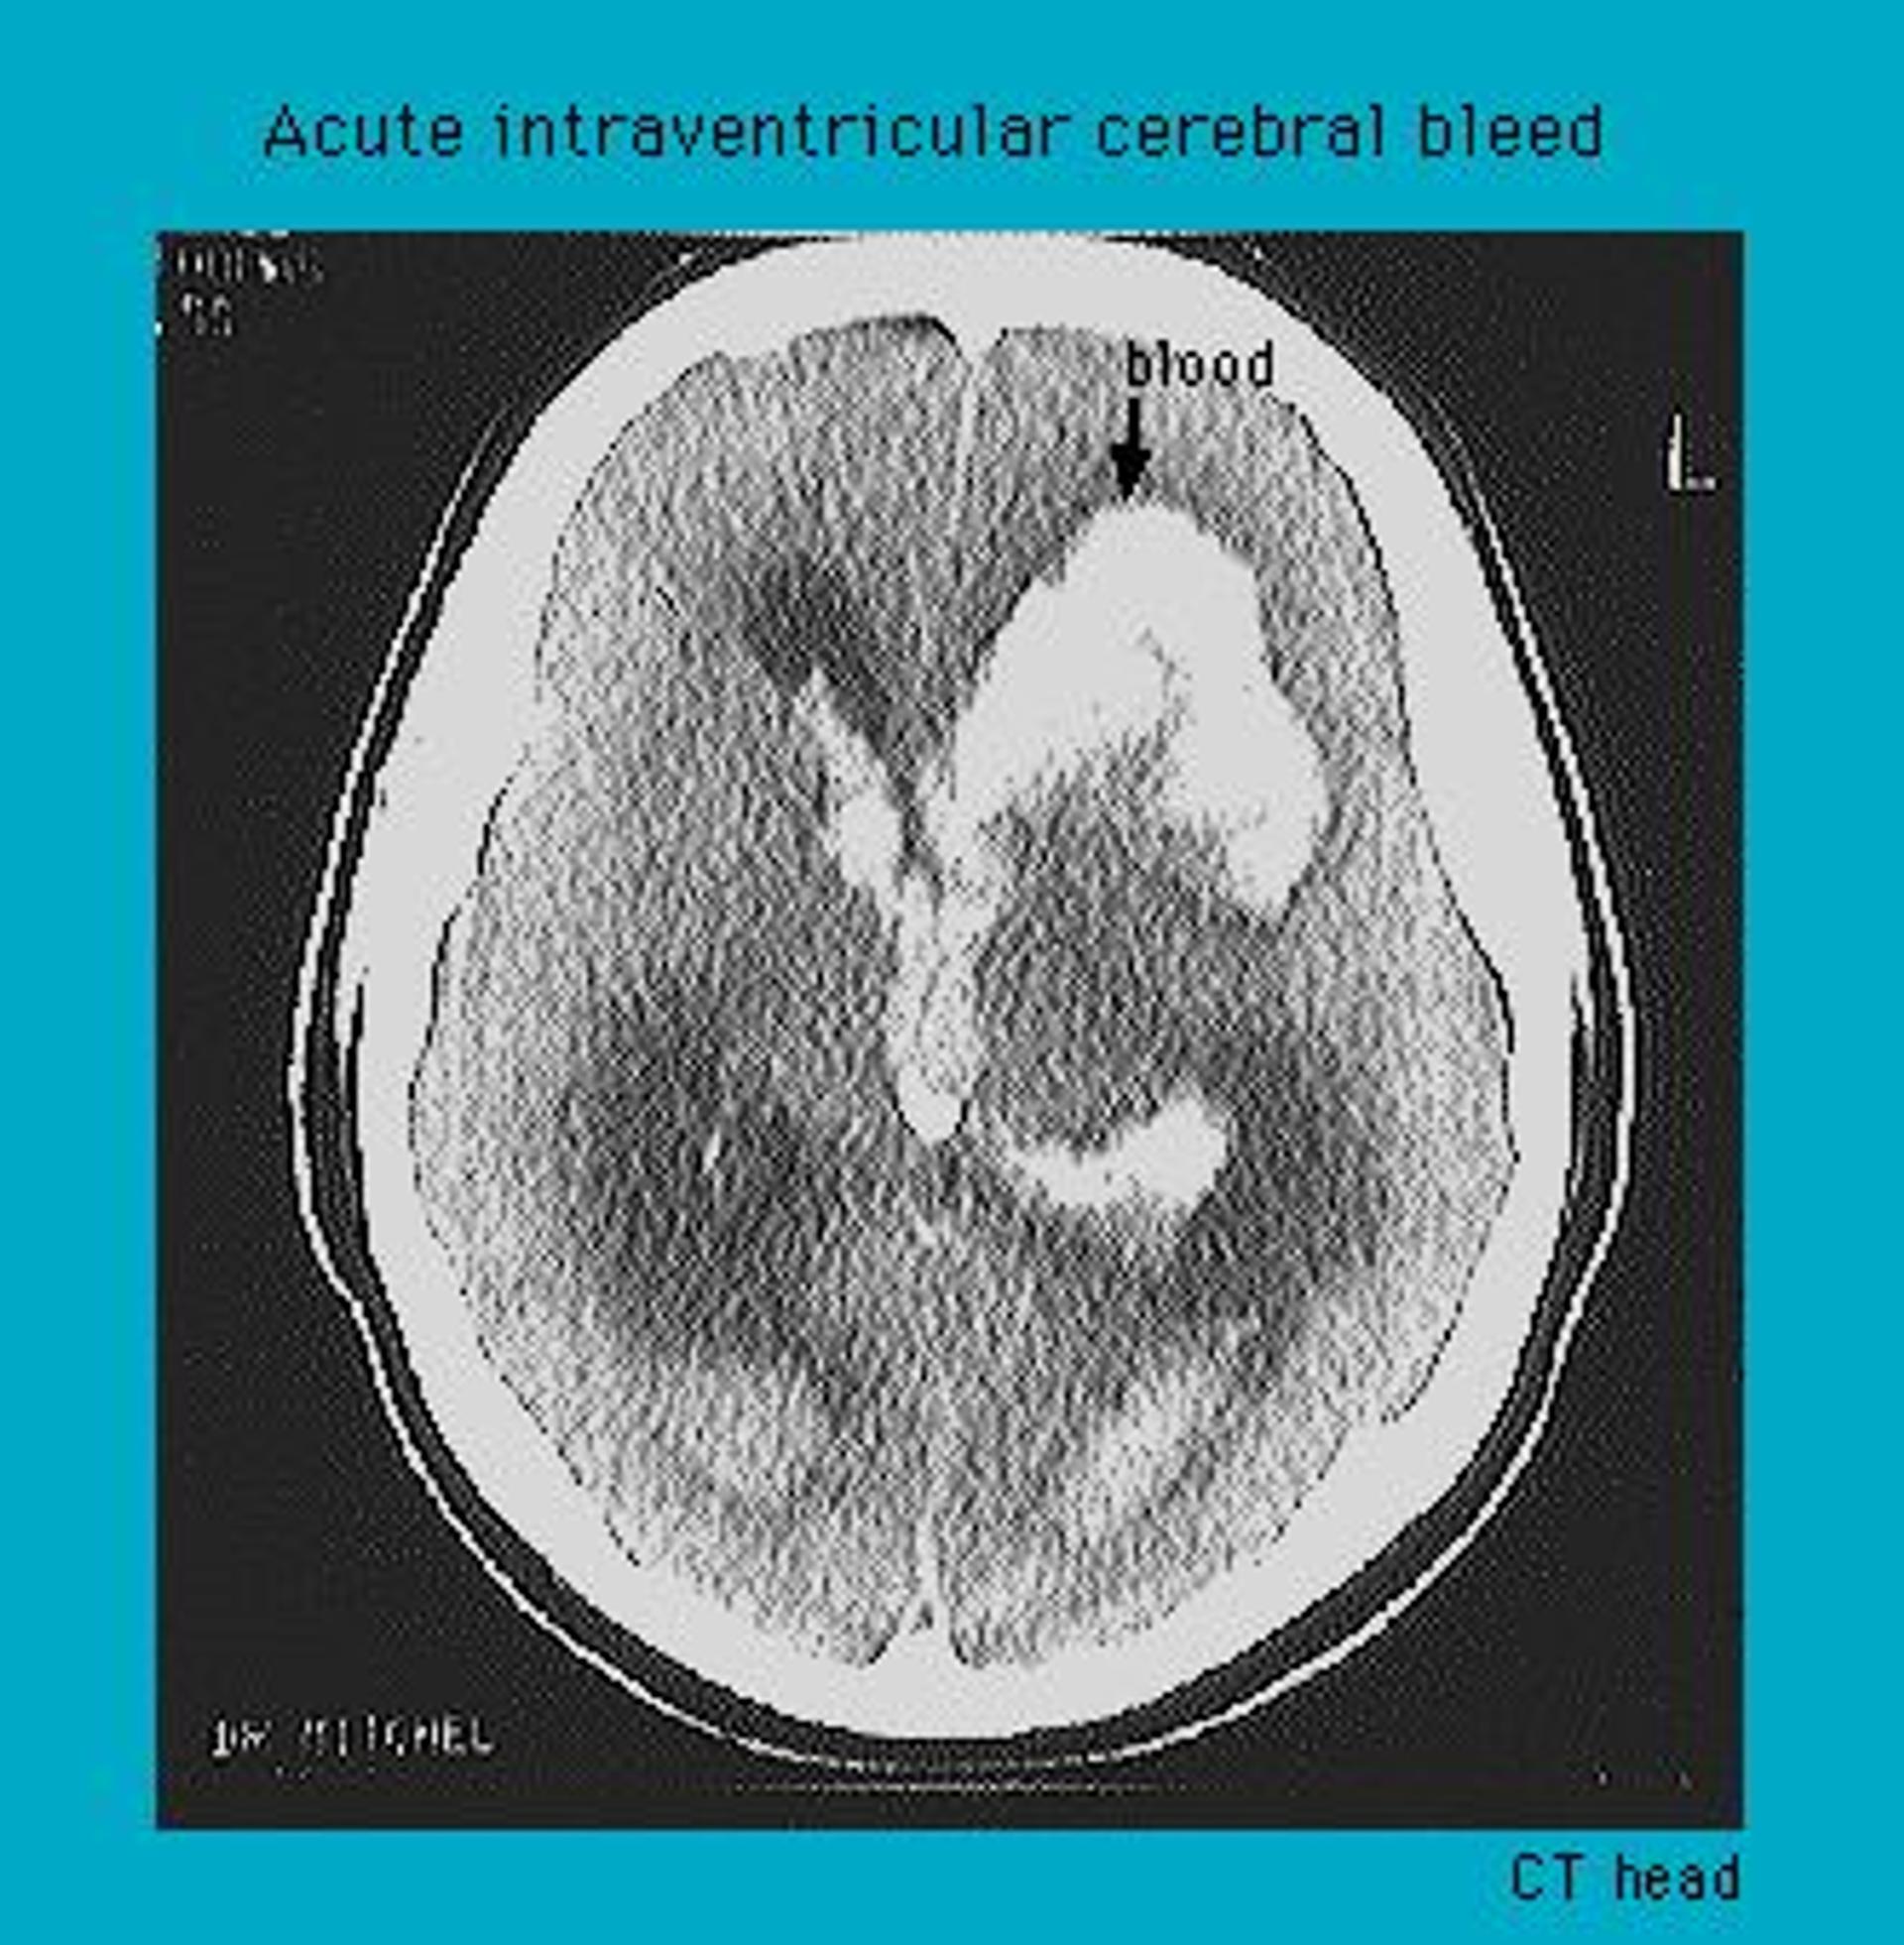

CT scan showing intraventricular haemorrhage